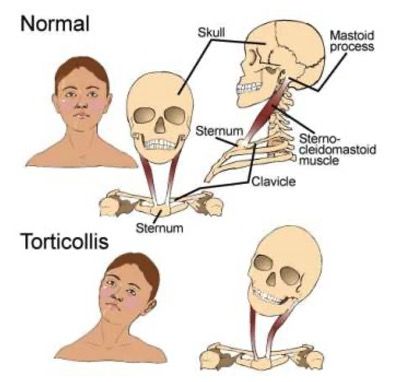

What is a Torticollis?

A common presentation for neck pain is when a patient has gone to bed feeling well and wakes up the following morning with a stiff sore neck. They often present to our office unable to turn their neck and in a significant amount of pain. Muscles in the neck will have significant spasms with this condition.

Another term for torticollis is a wry neck.

The cause of torticollis is still debated, however, there seems to be a significant link to incorrect posture, an activity that has caused strain to one side of your neck and to a cold draught blowing directly on the neck. There has also been research into there being a viral cause to torticollis. Whatever the cause is, be it one of these things or a combination – which seems to be most likely our treatment is similar for all.

When individuals have a torticollis there is always a significant amount of inflammation which is in both the joint and the surrounding soft tissues. This is best addressed by using ice on the area for ten minutes at a time. Having an adjustment as soon as possible when this occurs will help improve your range of motion and help you recover from the symptoms quicker. It is important when you have torticollis to continue to move your neck through the range of motion that you have, as this will prevent your muscles and ligaments from becoming tighter and worsening the condition.